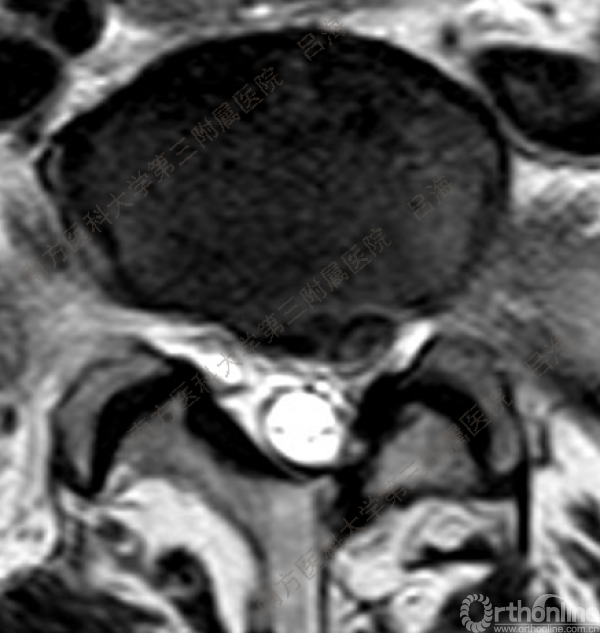

随着社会老龄化进程加快,胸腰椎退行性病变的治疗已经成为脊柱学术界的一个热点话题。MIS-TLIF手术可以治疗多种不同的胸腰椎退行性疾病,南方医科大学第三附属医院吕海教授结合病例为我们一一展示了该术式在治疗不同胸腰椎疾病时的具体手术过程。